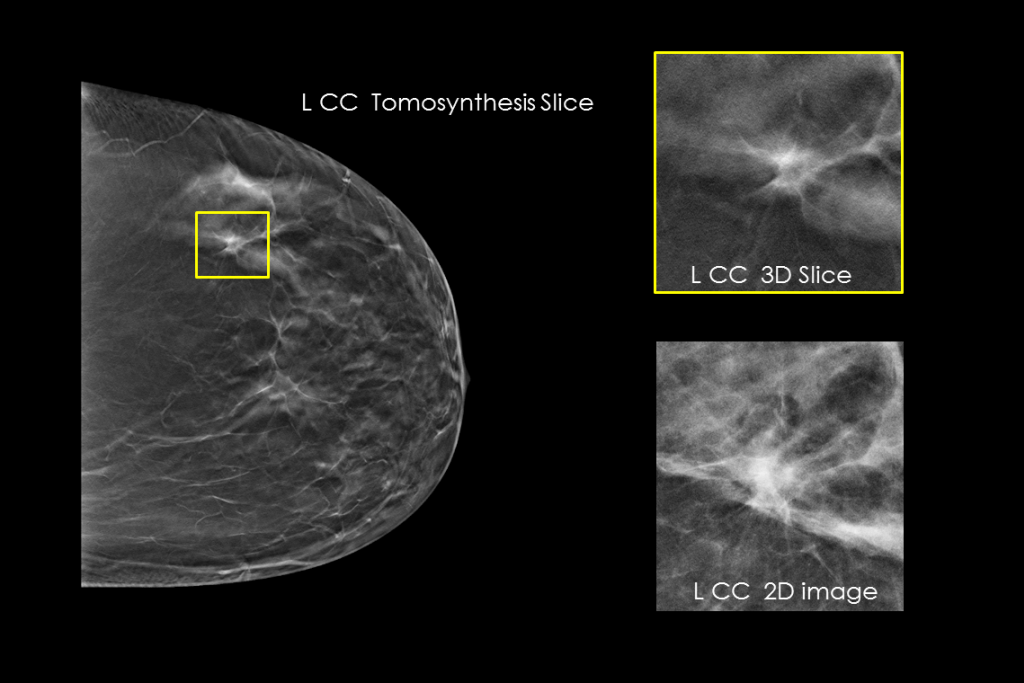

乳房検査マンモグラフィの臨床画像

疑わしい病変が見られる乳房検査の臨床画像